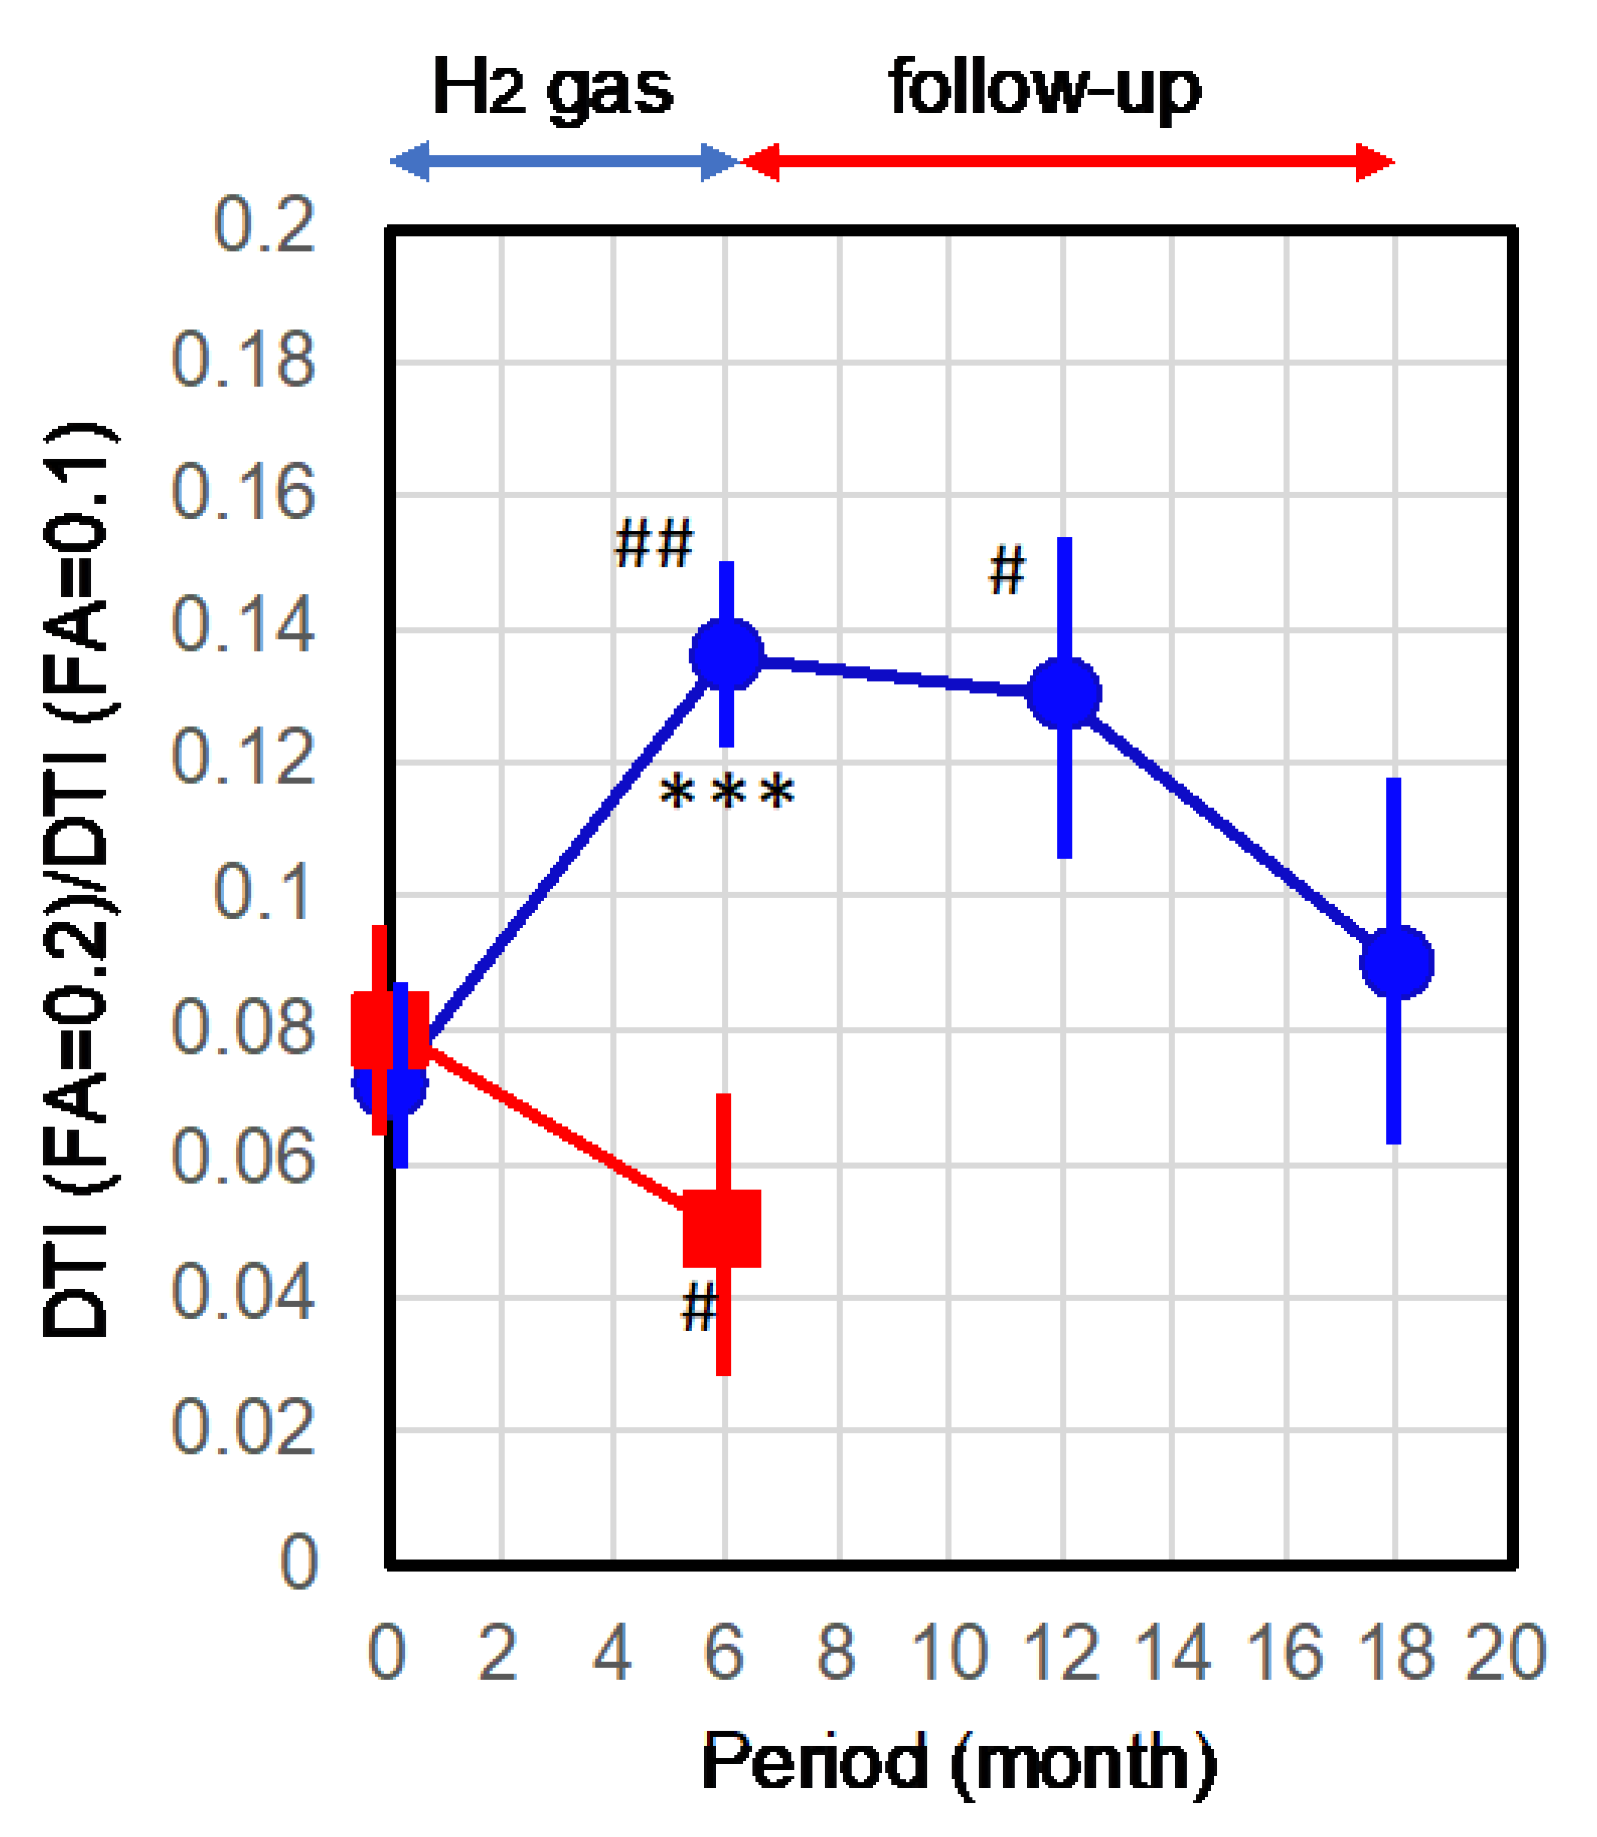

2.2. Improvement of Neurons by H2 Inhalation as Assessed by Diffusion Tensor Imaging

4.6. Measurement of the Integrity of Neurons by Diffusion Tensor Imaging